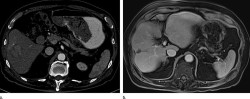

Un primer ensayo clínico en humanos demuestra una mejora en el tratamiento con radiación del cáncer de hígado

Una nueva investigación ha demostrado, a través del primer ensayo clínico en humanos, que el actual tratamiento del cáncer del hígado mediante radioterapia dirigida administrada con la ayuda de perlas de vidrio que emiten radiación se puede aumentar al infundir microburbujas (pequeñas burbujas de gas rodeadas por una capa de lípidos) en el hígado y hacer estallar esas burbujas por ultrasonido, según publican los investigadores en la revista `Radiology`.